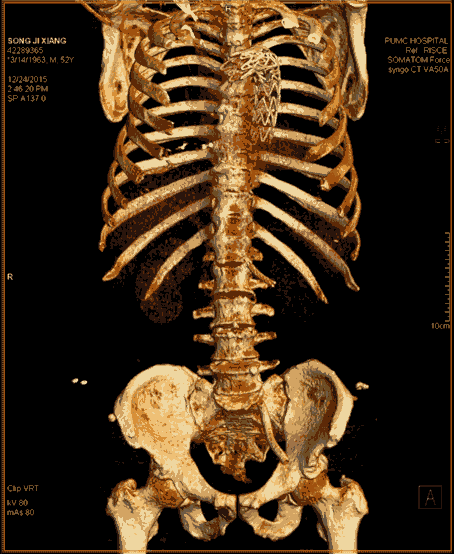

8. 類DSA成像:

傳統DSA成像有創而且操作復雜、掃描范圍受限。

SOMATOM Force 突破技術界限,將血流評估覆蓋范圍擴大至80cm,特別適合大范圍下肢血管疾病診斷,一次掃描一次注射即可無創精確判斷病變,更加精確地制定臨床決策,選擇合理的治療方法。

△80厘米無創CT DSA,影像決策診療